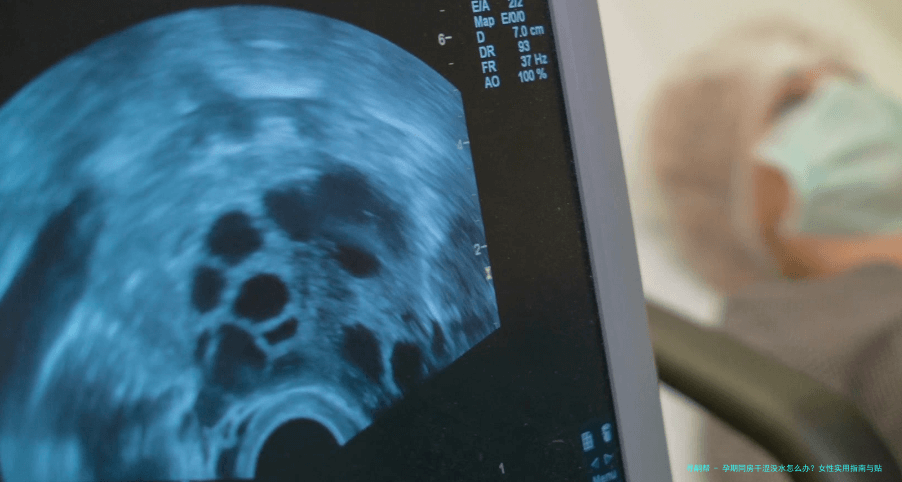

首先,咱们得明白为啥会出现这种情况。孕期身体变化大,激素水平波动是主因。雌激素和孕激素的升降,直接影响阴道分泌物的多少——说白了,激素一乱,"润滑系统"就容易罢工。据近年医学数据,超过25%的孕妇因激素变化导致阴道干涩,尤其在孕中期和晚期更明显。其次,心理因素也不能忽略;怀孕后,你可能更焦虑或疲劳,这些情绪会抑制性欲,让身体"没状态"。另外,身体不适如尿频或背痛,也会间接导致干涩。我记得有个案例,一位准妈妈因为担心伤到宝宝,心理压力大,同房时总是紧张,结果干涩问题更严重了。所以,原因多种多样,但大多是可逆的,别太自责。